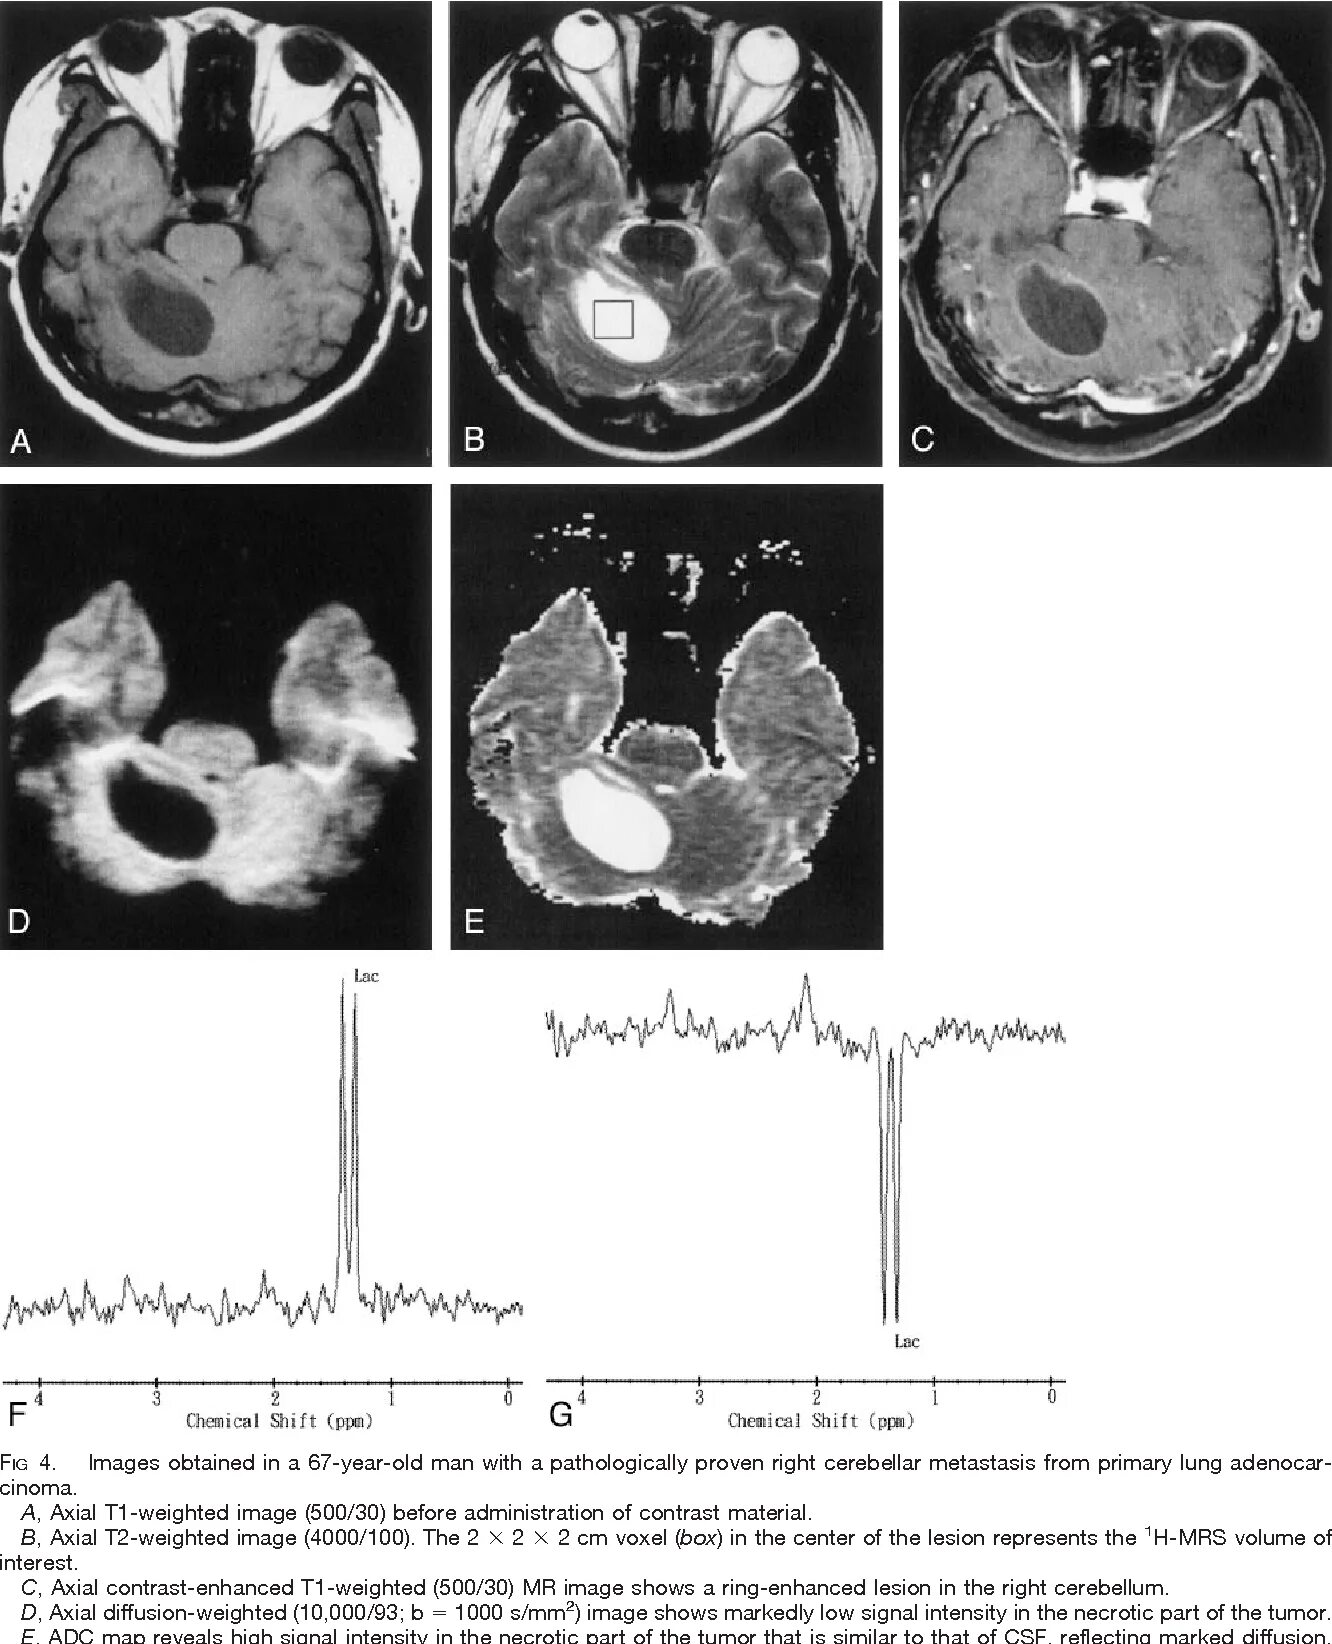

Дифференциальное мрт